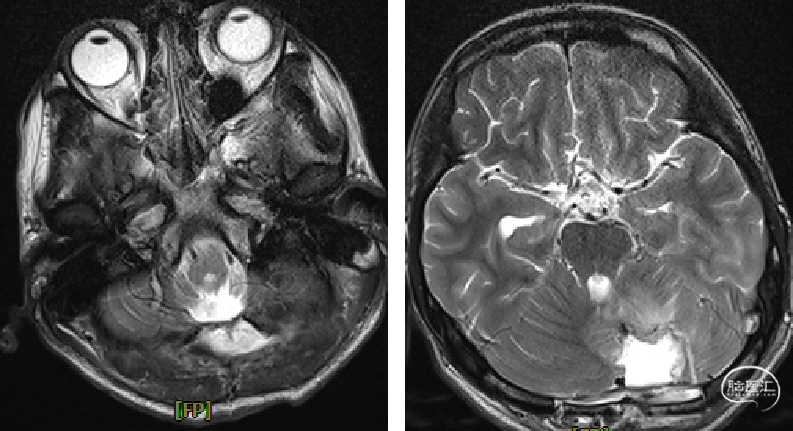

术前MRI

image.png

诊断及手术方式

术前诊断:

1.小脑、延髓占位(血管母细胞瘤)

2.梗阻性脑积水